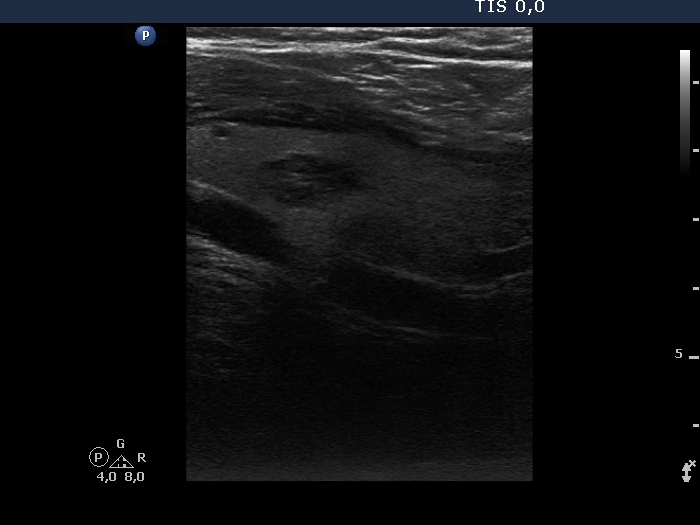

Thyroid cancers - case 1041 (ultrasonographic picture 6)

Left lobe, longitudinal view.